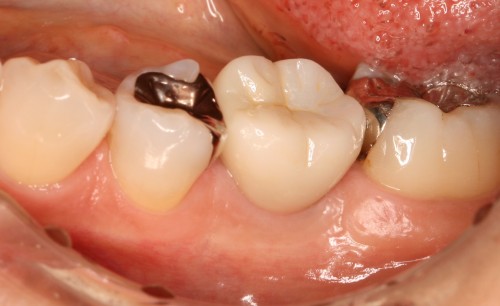

インプラント埋入前